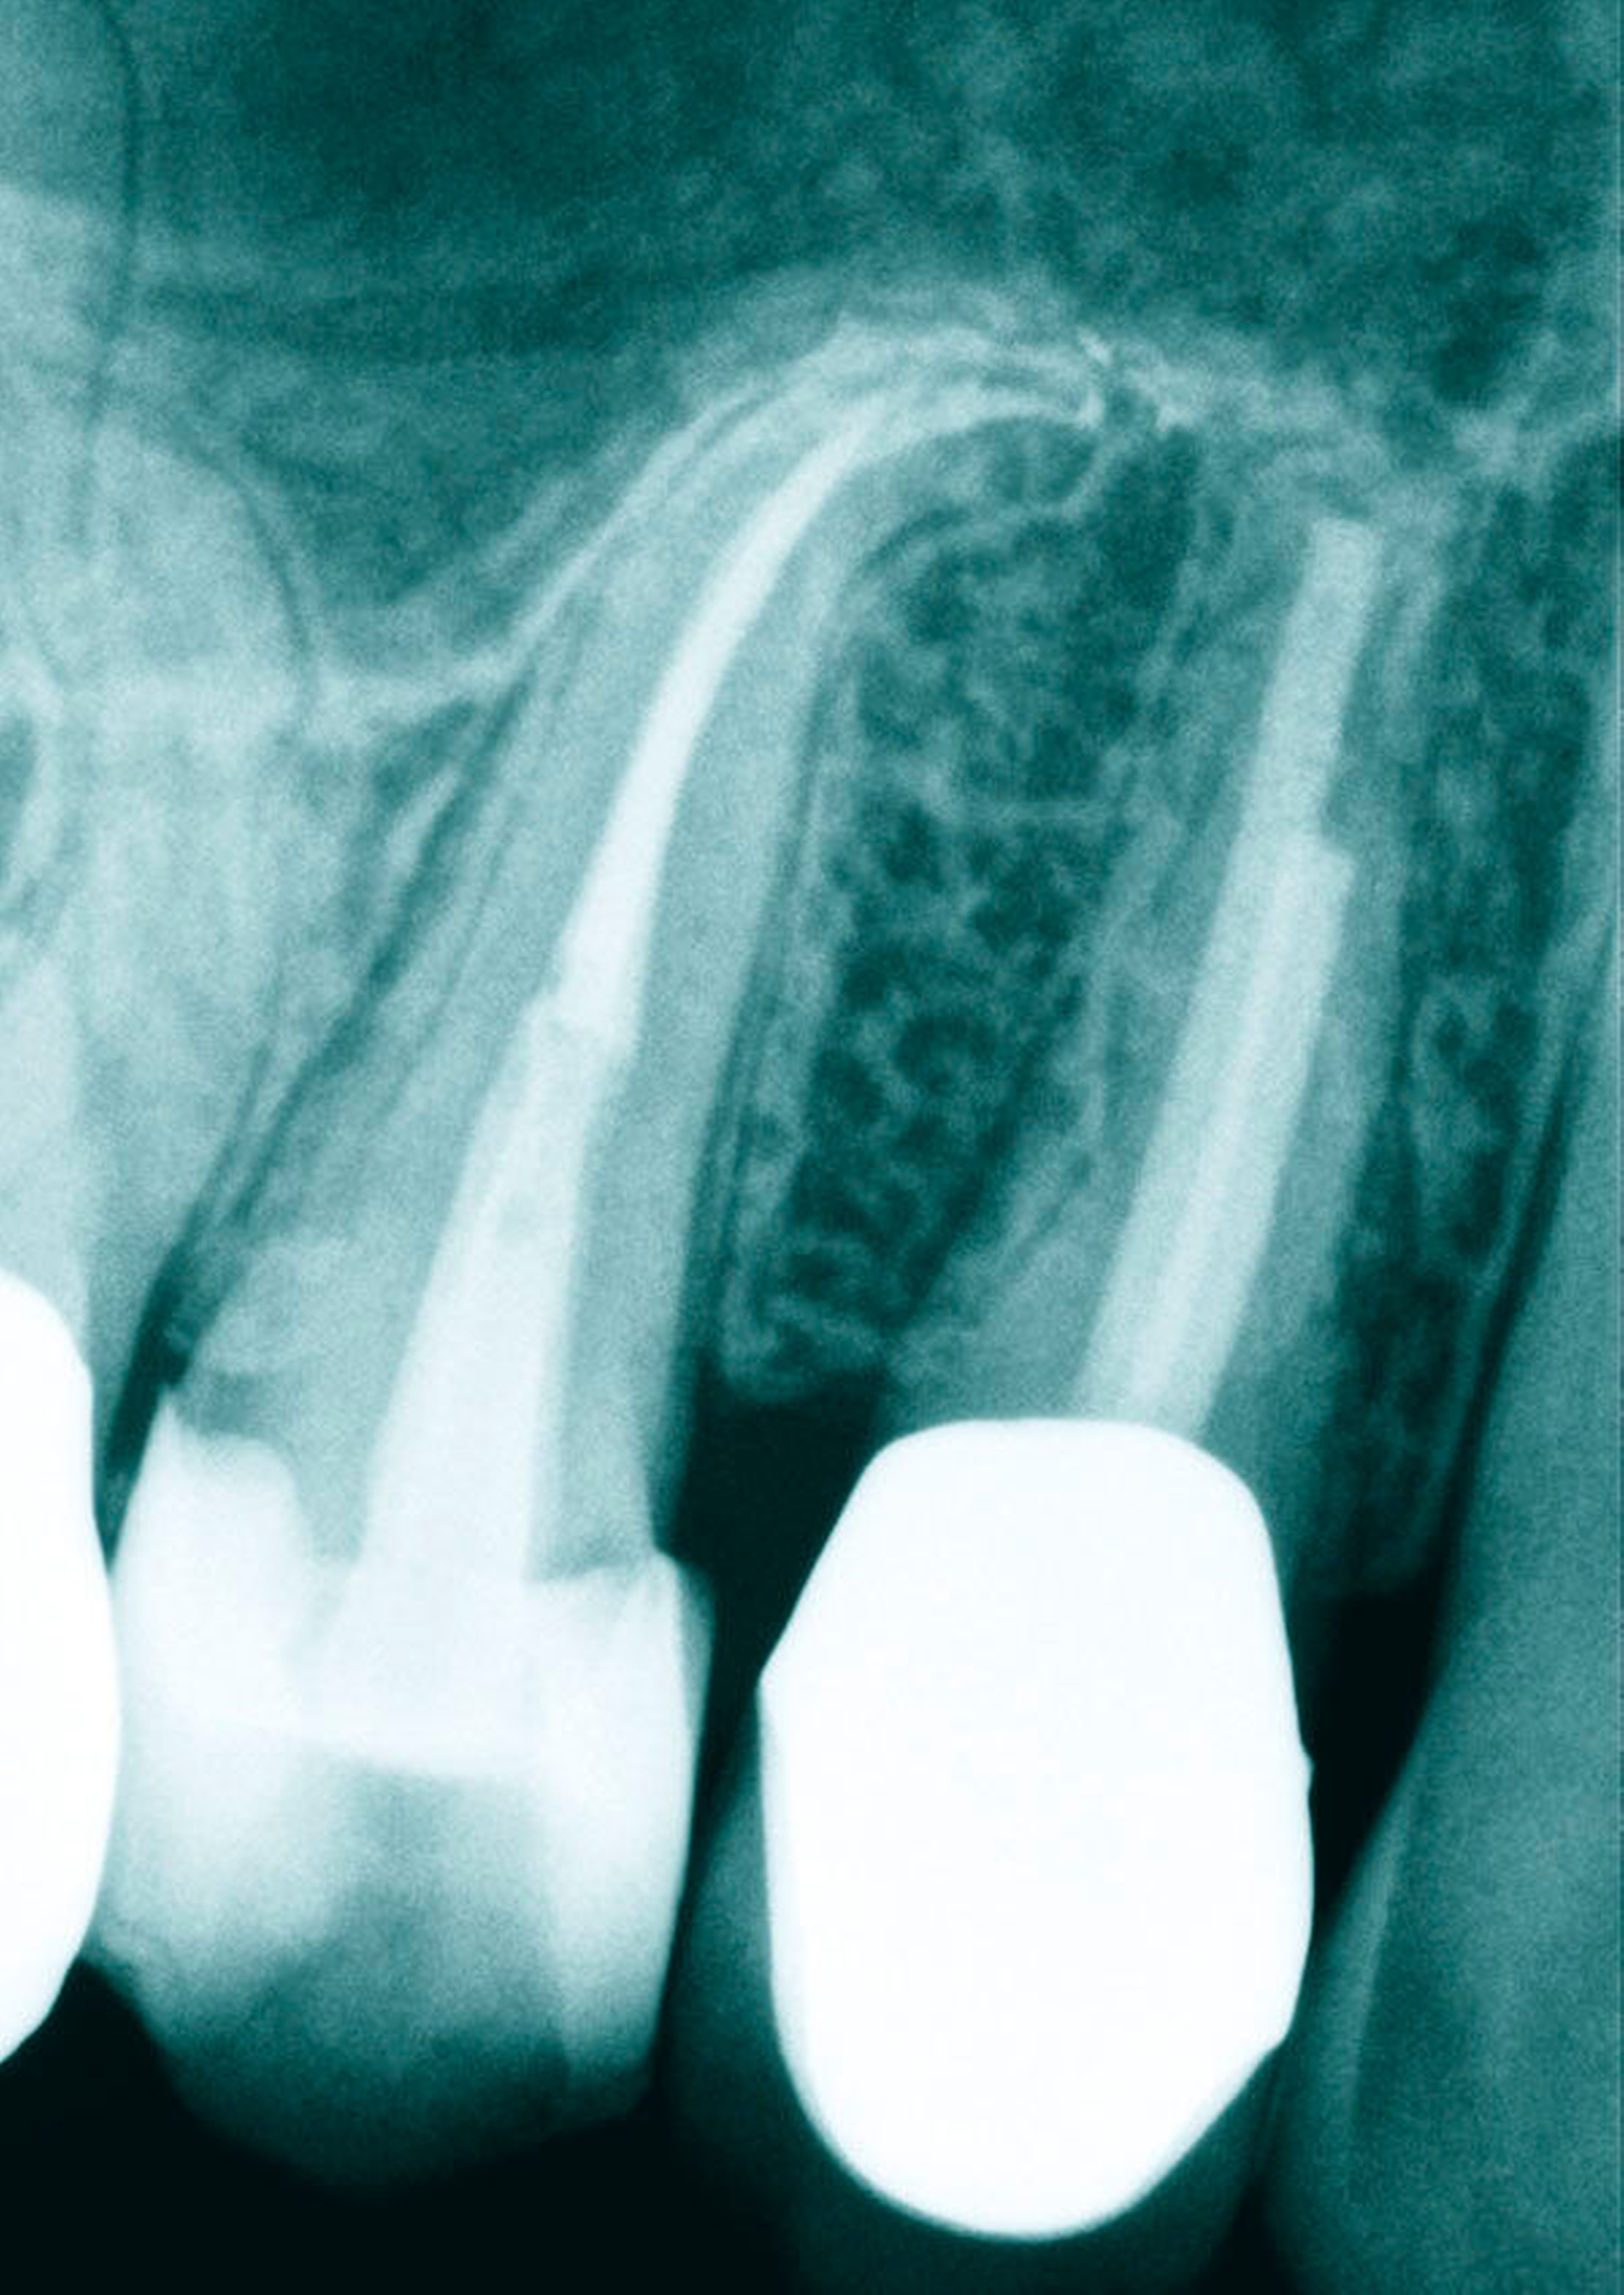

Beim ersten Prämolaren sind fast immer zwei vollständig getrennte Kanalsysteme aufzufinden. Von koronal nach apikal sind die Kanäle meist rund im Querschnitt – nach eigenen Beobachtungen bei hunderten von eingescannten Zähnen sind die Kanalquerschnitte des ersten oberen Prämolaren mit zwei Kanälen im Vergleich zu allen anderen Kanälen im menschlichen Gebiss am ehesten als rund zu bezeichnen – und werden sehr schmal im apikalen Bereich mit zum Teil erheblichen Krümmungen (Abbildung 2).

Die Krümmungen folgen bei beiden Zähnen in der Regel dem distalen Krümmungsmerkmal. Eine starke Ausdehnung der Kieferhöhle scheint jedoch für starke apikale Krümmungen der Wurzeln nach mesial oder distal verantwortlich zu sein. Ebenfalls nicht selten anzutreffen sind Doppelkrümmungen der Wurzeln (Abbildung 3).